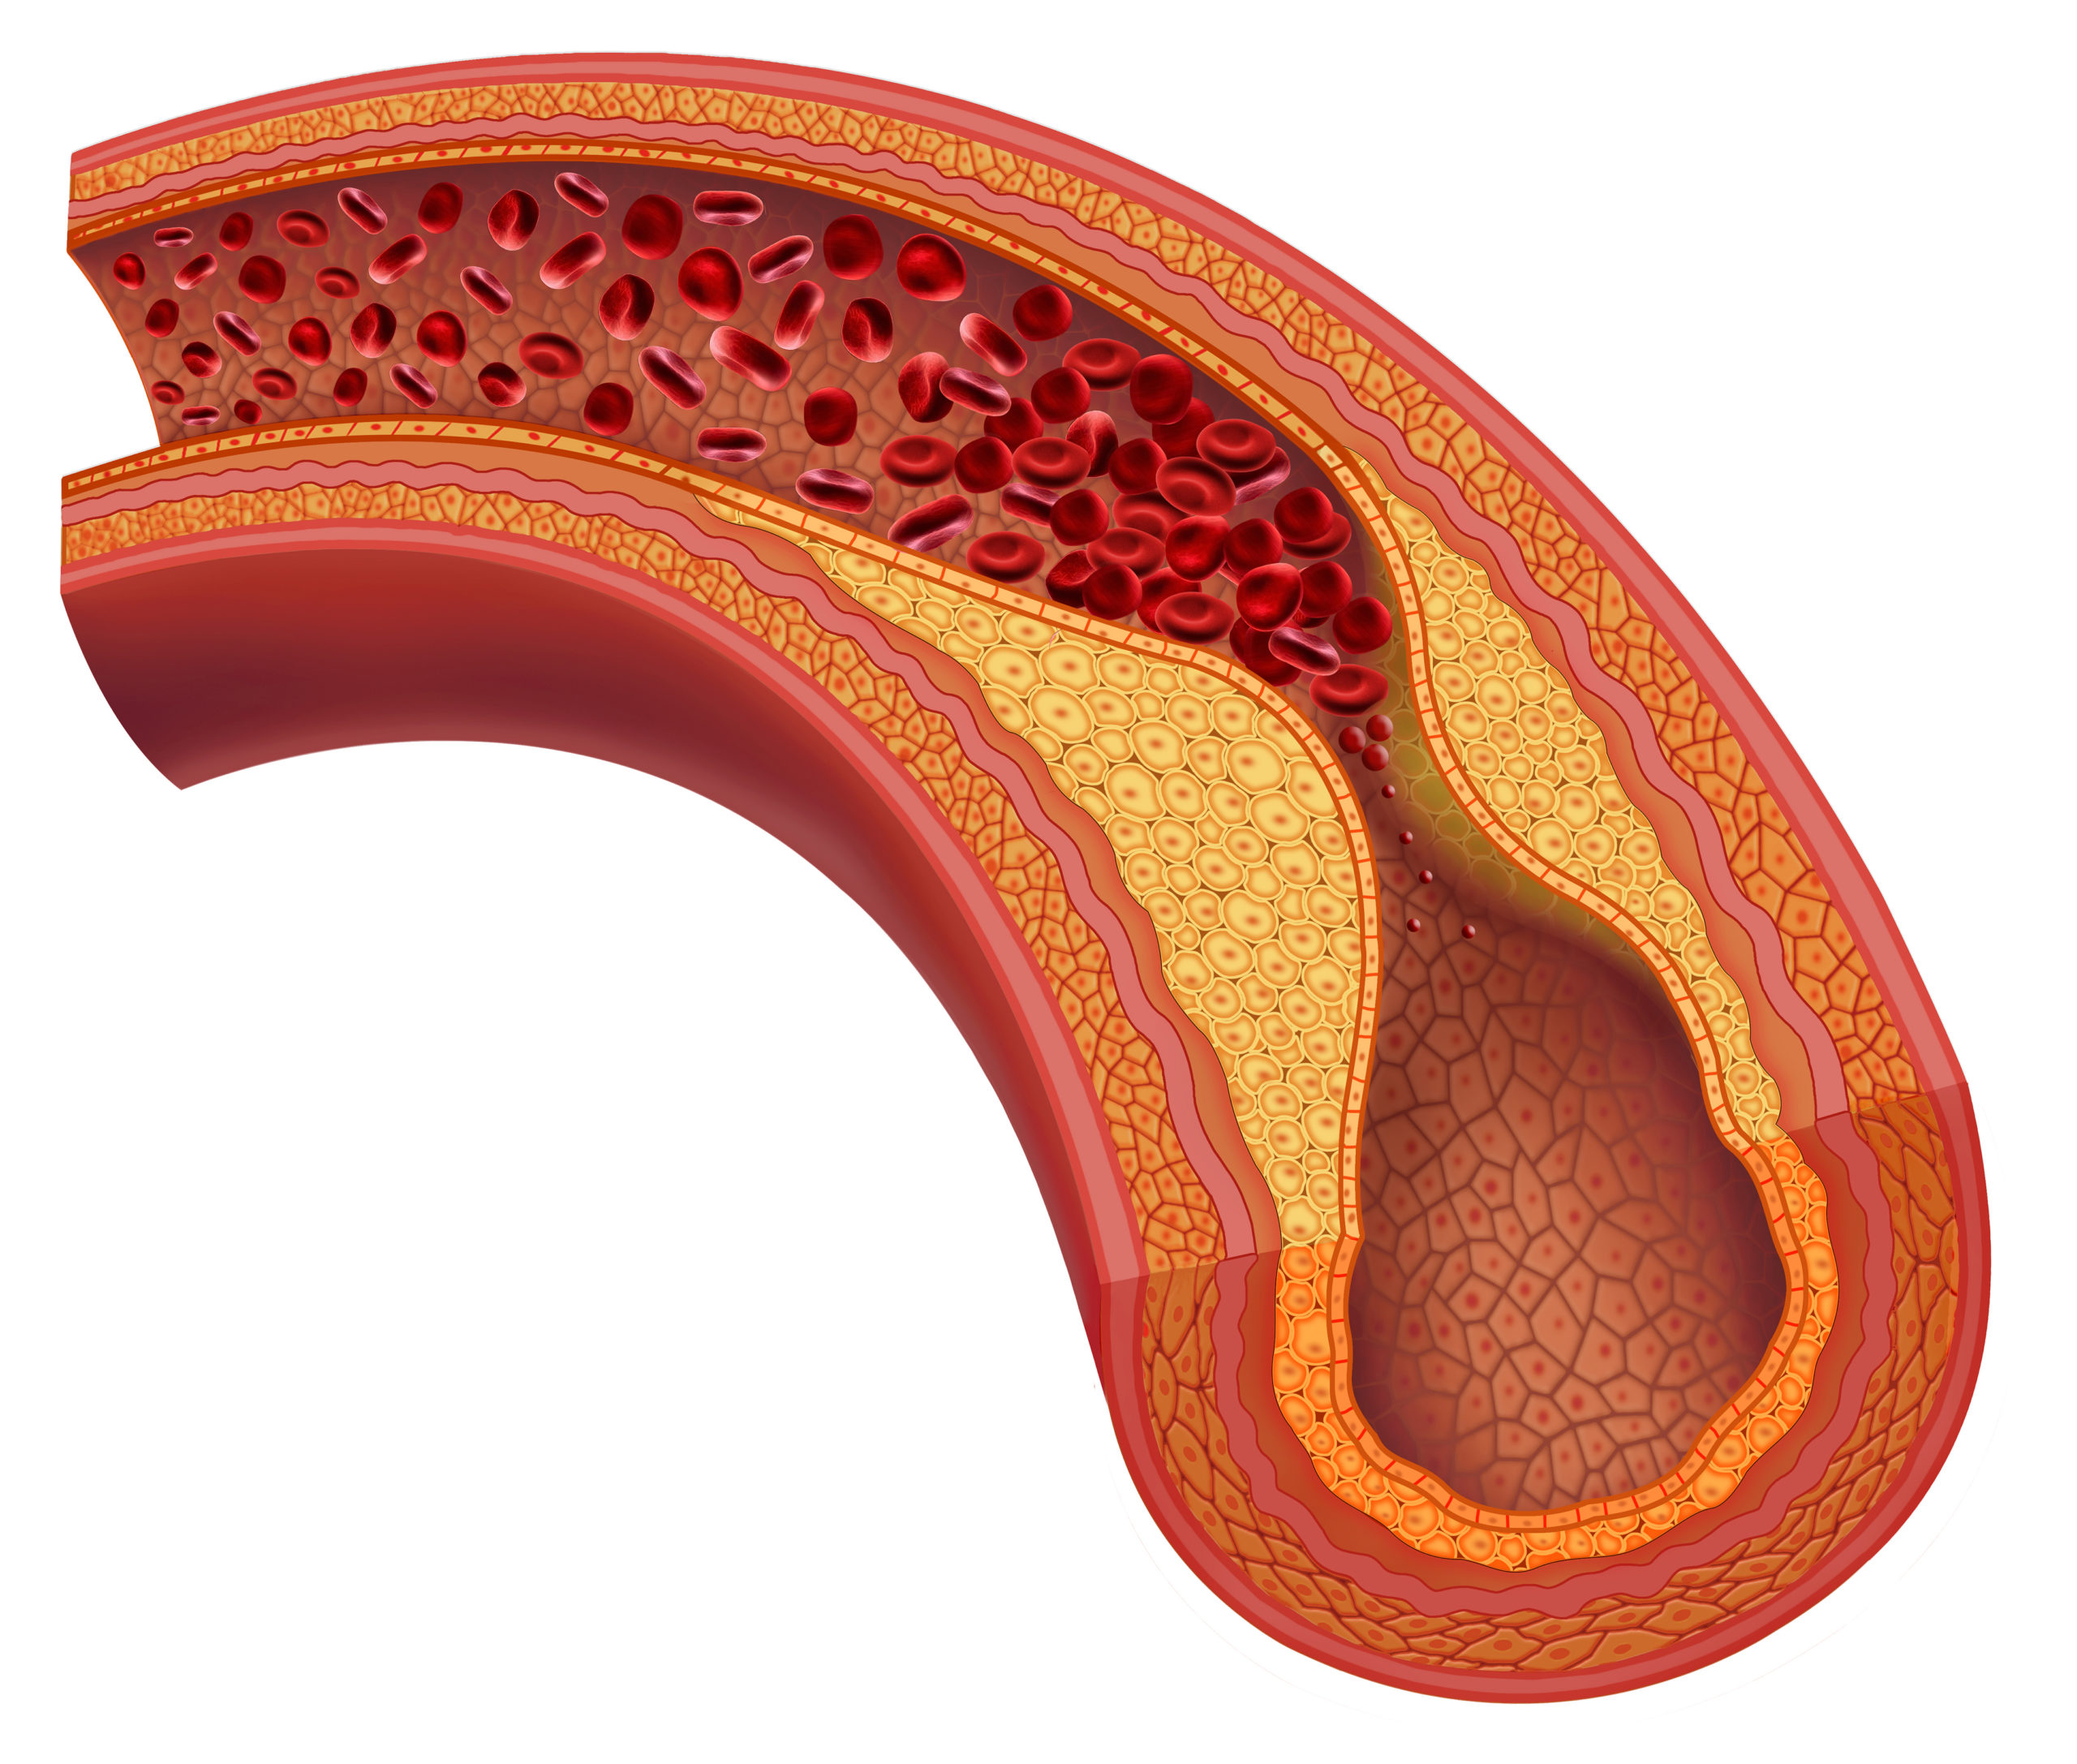

Researchers, led by Yi Qin, MD, investigated the use of the TurboHawk atherectomy in the treatment of in-stent ...

Coronary Artery Calcification Severity Is Associated with Rate of Adverse PCI Outcomes